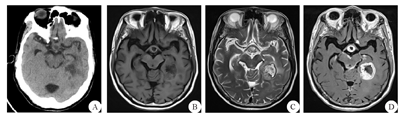

患者 男,64岁,因阵发性头痛、肢体抽搐1月余于2020年1月12日入院。既往体健,否认结核等病史,近期亦无发热、咳嗽情况。体检:体温36.8 ℃,血压120/80 mmHg(1 mmHg=0.133 kPa),神志清楚,记忆力减退,反应迟钝,余未见明显阳性体征。实验室检查:血常规、血清肿瘤标志物筛查等均为正常值,结核T细胞斑点试验(-)。胸腹部CT平扫、肝胆胰脾肾超声等检查未见明显异常。颅脑MRI提示颅内脑实质及脑膜多发异常强化病灶(图1),术前诊断考虑转移瘤可能性大、结核待排。综合考虑手术风险及重要神经功能损伤、同时明确病理诊断等因素后决定切除较大的左颞枕叶病灶。采用神经导航引导下经左颞枕马蹄形切口入路全切除左侧颞枕叶占位病变,术中见病变组织呈鱼肉样,色灰白,质地偏韧,边界不清楚,血供较丰富,病变内部含坏死组织。术后病理诊断为GS:肿瘤细胞呈梭形,胞界不清,胞浆嗜酸,核梭形或不规则形,呈片状或束状分布,可见瘤巨细胞;小血管呈簇状增生,可见栅栏状坏死(图2)。免疫组化染色显示胶质纤维酸性蛋白及波形蛋白阳性。术后予以防治癫痫、补液等治疗,2周后患者头痛症状改善,转肿瘤科行辅助放疗和替莫唑胺化疗。术后第5个月电话随访,患者病情恶化放弃继续术后辅助治疗。

A:颅脑CT平扫,左侧颞枕叶、海马、大脑大静脉池、桥前池、鞍上池不规则低密度影;B:颅脑MRI轴位T1加权像,前述部位见多发结节状片状稍长T1信号;C:颅脑MRI轴位T2加权像,前述部位见多发结节状片状稍长T2信号,部分病灶周围可见轻度水肿;D:颅脑MRI轴位增强扫描像,前述部位见明显片状、环形强化,内可见片状无强化区,部分邻近脑膜受累

GS是中枢神经系统罕见的恶性肿瘤,占全部胶质母细胞瘤的1.8%~8.0%,少数可以在原发时即为GS,多数是胶质瘤术后或是放疗后继发演变而来[2,3],组织病理学表现为胶质瘤和肉瘤的特点[4,5]。胶质瘤成分上为神经胶质纤维酸性蛋白阳性;肉瘤部分富含网状纤维,由神经胶质纤维酸性蛋白阴性的梭形细胞密集束状排列而成,细胞核有不典型性,核分裂象多并有坏死,是病理诊断GS的重要依据。发病人群以中年男性为主,婴幼儿亦可发病。GS与胶质母细胞瘤和星形细胞瘤的病程经过及临床症状相似,多数病程短且无明显特异性表现,部分患者存在神经轴及肝、肺、淋巴结等颅外转移倾向,这主要由其肉瘤部分决定[6]。GS影像学表现复杂多样,确诊仍需病理定性,典型影像学特征为[2,7,8,9]:GS呈类圆形或不规则形;CT表现与一般恶性胶质瘤类似;MRI多表现为T1像呈低信号,T2像呈混杂稍高信号或高信号,信号不均,中央部分坏死囊变,瘤周不同程度水肿,占位效应明显;增强扫描呈环形、花环状强化,部分呈不均匀强化。目前GS多见于大脑半球,特别是颞叶,绝大部分病灶为单发且多靠近脑表面,仅有少数个案报道称有多发GS[10,11]。本例患者病灶数量远多于目前已有报道,病灶分布于左侧颞枕叶、海马、大脑大静脉池、桥前池、鞍上池,呈现颅内多发脑实质及脑膜异常强化病灶,弥漫多发样改变,病灶数目极为罕见,病灶所在位置亦少见。由于GS临床相对较少的特性且该病影像表现有时与大脑半球的其他占位性疾病,如胶质母细胞瘤、原发性中枢神经系统淋巴瘤、脑脓肿、结核、梅毒、转移瘤等极为相像,因此术前诊断较为困难,极易出现误诊。本例患者术前就曾数次在外院及我院被诊断为转移瘤可能性大、结核待排。由于术前考虑恶性病变可能,病灶多发且分布较散、部分位置深在,全切可能性不大;但为了一定程度上解除病灶占位效应缓解颅高压症状并明确病理诊断,最终选择孤立的颞枕叶大病灶进行切除。术中病理亦考虑高级别胶质瘤可能,故没有继续另行术口切取其他部位病灶以避免增加医源性创伤。本例患者无颅脑肿瘤及放射治疗病史,其发病年龄、性别及肿瘤原发部位与既往文献报道相似,故颞枕叶病灶属原发性GS可能性较大。与胶质母细胞瘤相比,GS更易发生颅内外转移,但仅根据影像学表现难以准确判断海马、脑池等处的病灶是否是脑脊液播散转移而形成,进一步研究需行更为详实全面的病理检查。